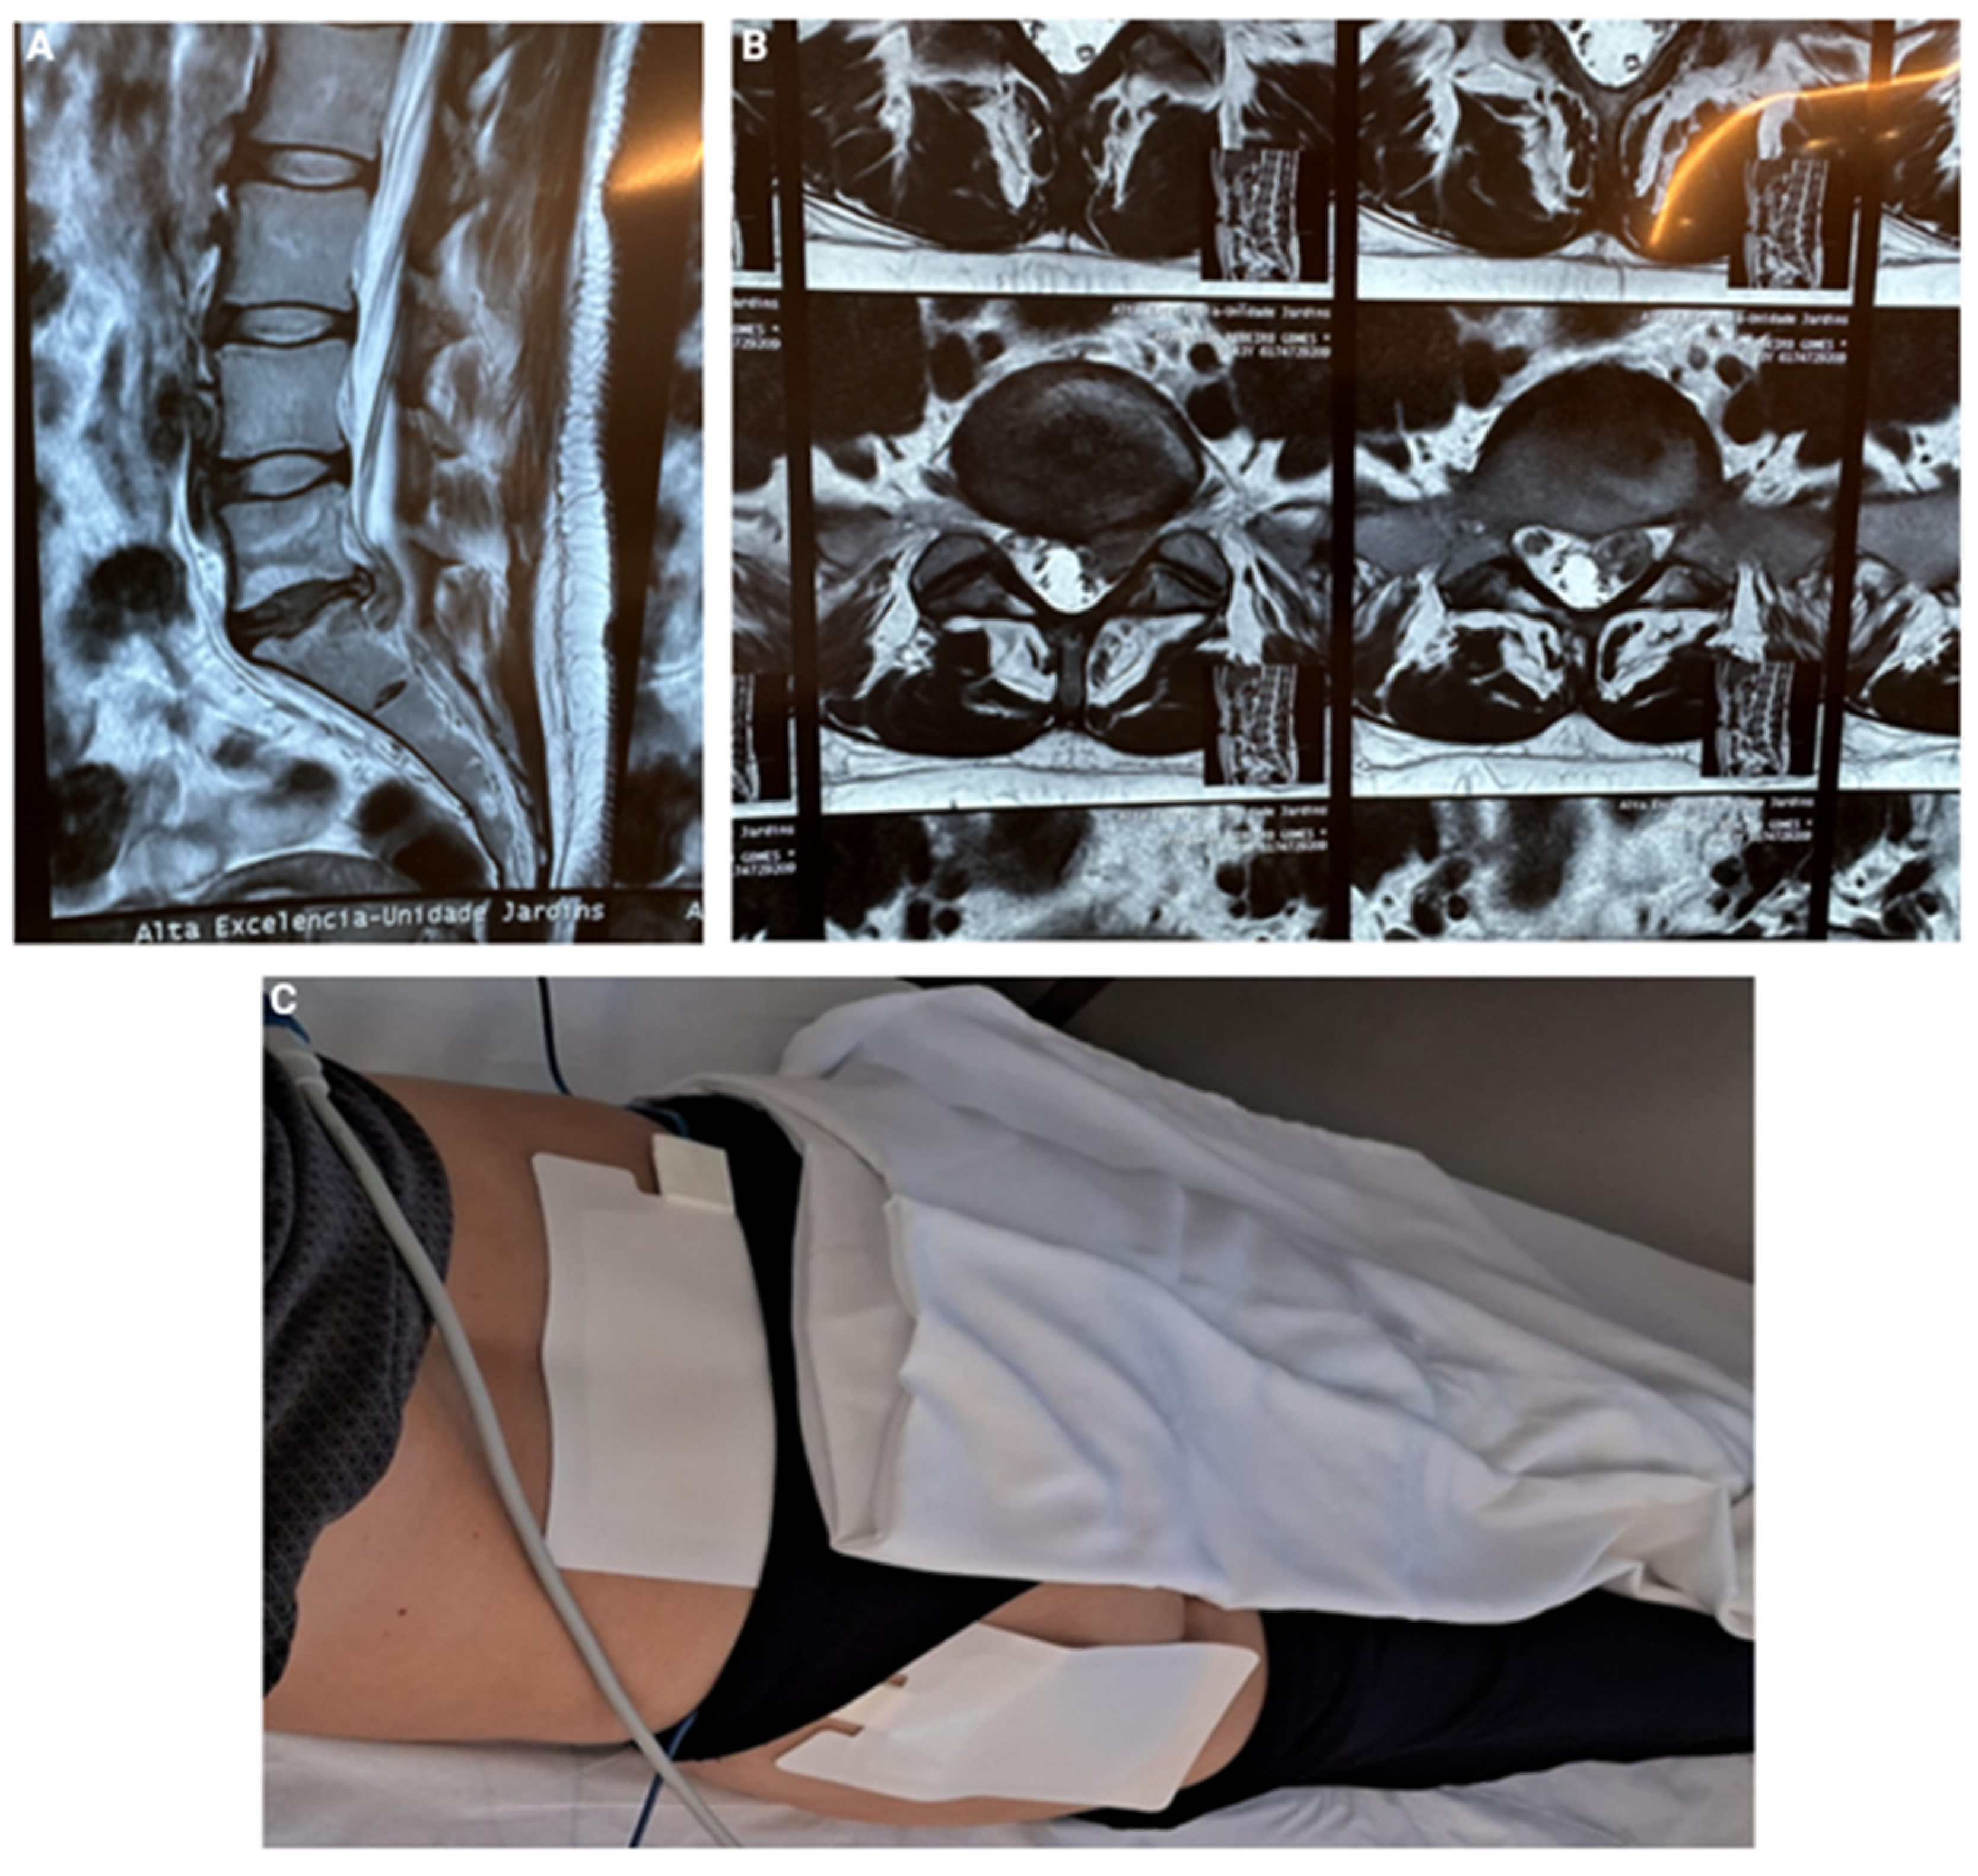

5. CASE 4: Lumbar Disc Herniation with Compression and Central Stenosis

N.M., a 32-year-old woman, was referred to our clinic in São Paulo, Brazil, with complaints of low back pain radiating to the left lower limb, accompanied by numbness, which promoted difficulty sitting for extended periods at work. Her MRI revealed a large disc herniation at L4-5, compressing the central canal (Figure 5). After 30 days of conventional conservative treatment without improvement, we offered, with her consent, the application of transcutaneous STP Radiofrequency as a therapeutic option. The treatment involved placing medium adhesive patches at the hernia level and along the sciatic path in the left buttock, where the pain was radiating. We used a Spring2® generator with medium patches, set at 1.4A for 15 minutes, delivering 108V of STP (Figure 5).

The same procedure was repeated in 15 days, and 6 weeks after the first application, maintaining intervals based on the therapeutic response as previously described by Sluijter et al. in 2023 [13], resulting in a total of 3 sessions. By the third visit for the final session, the patient was completely pain-free, with a VAS score of 0, no numbness, and had fully regained her ability to sit at work normally. At a follow-up evaluation 60 days later, she remained pain-free and continued to demonstrate excellent functional outcomes.

Figure 5. A) MRI revealed a large disc herniation at L4-5; B) Central canal compression; C) TC-PRF patches application for lumbar disc herniation with left limb irradiation.